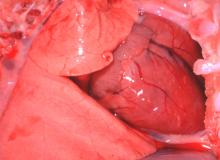

1. 試驗豬接種病毒後56小時突然發生呼吸困難。 2. 猝死仔豬有典型虎斑心病變 (圖1)。 3. 攻毒後42小時舌頭產生水泡病變 (圖2)。 4. 攻毒後72小時蹄冠產生水泡。 三、 組織病變: 1.

斃,最具特徵性變化為心肌急性帶狀壞死,肉眼病變呈黃白色桿狀樣壞死斑,又稱虎斑

心。依據文獻資料顯示 FMDV 可大量自乳汁排出,母豬感染 FMDV 後,哺乳豬吸吮含有FMDV 乳汁,大量病毒侵犯仔豬心肌,造成心肌的壞死。為進一步了解本病毒對初生仔